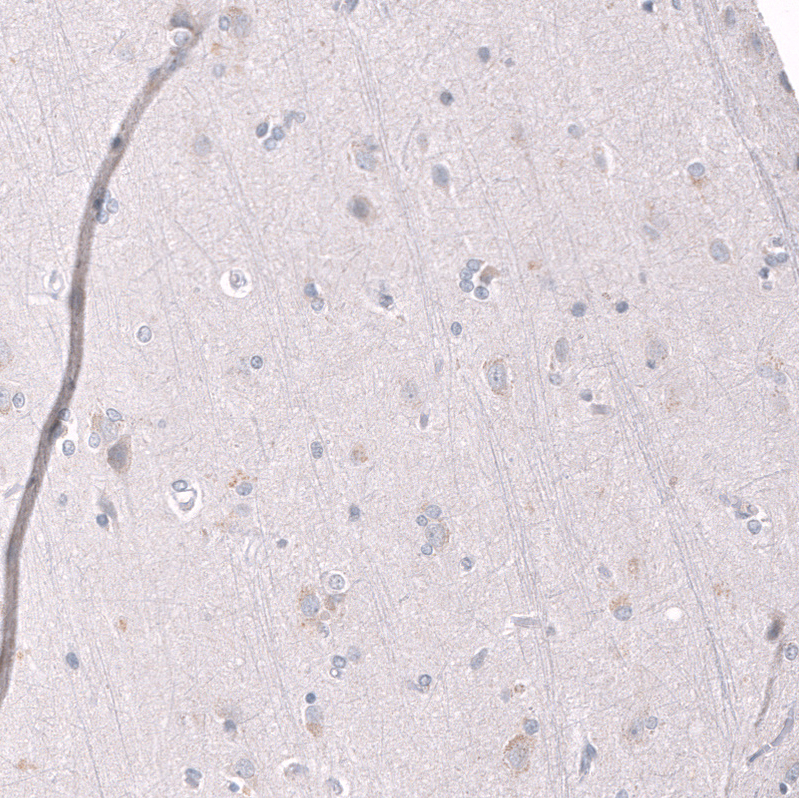

Immunohistochemistry analysis in human testis and cerebral cortex tissues using AMAb91752 antibody. Corresponding EZH2 RNA-seq data are presented for the same tissues.